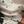

第二周期:做的是自然周期,2次月经后,(7月18日开始月经)第十一天到医院,开始监测排卵。第十四天排了卵,医生开了安琪坦,每日两粒上阴道,也就是移植前三天就开始上药了。8月6日移植囊胚2枚(4枚冻胚全部解冻养囊,成2枚),第6天,即8月11号,我们医院要连移植日当日算。测出意念灰,超级超级淡的水印,逐日加深,12天官方好孕,b-hcg448.7。移植26天一超宫内单活胎,有少量宫腔积液和黄体囊肿,具体数值看图。37天2超宝贝正常发育,积液消失,囊肿未见。